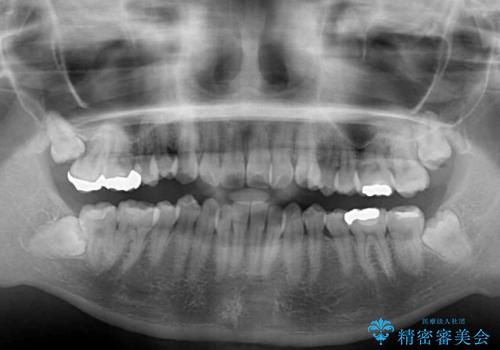

- 上下前歯のデコボコを気にして来院された患者様です。

インビザラインによる上下歯列の側方拡大と後方移動、IPR(歯と歯の間を削る)にるスペースの獲得により歯列を整えることとしました。

右上の小臼歯は歯根癒着をしており、様々な方法を試みるも動かすことができませんでした。

それでも奥歯のかみ合わせに不自由はなく、歯列をきれいに整えることができました。